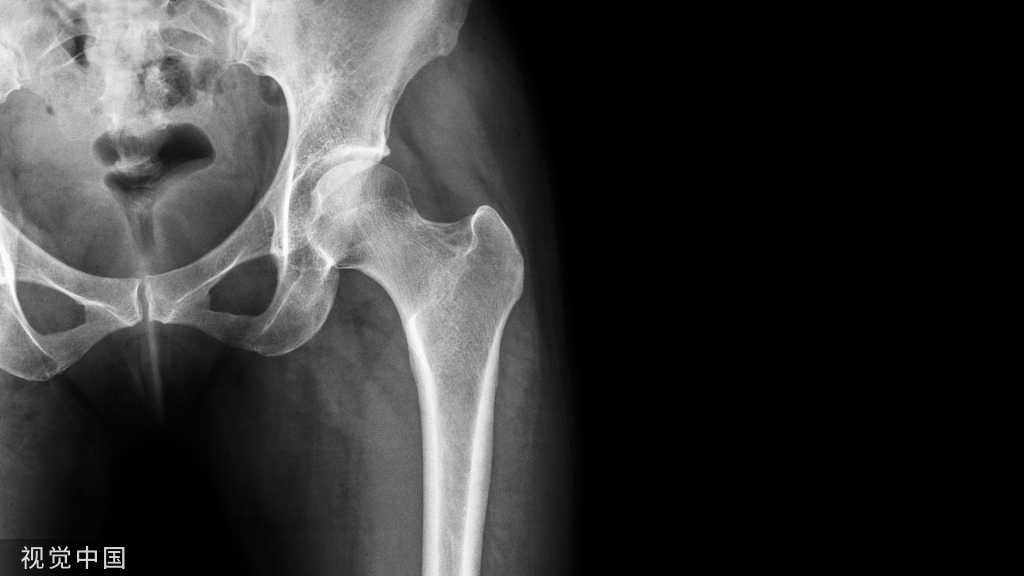

X线检查,创伤性膝关节滑膜炎骨质多无异常,或者有退行性改变,或者有关节内游离体。关节积液量多可见关节囊膨胀影。

膝关节软组织肿胀,髌下脂肪垫消失